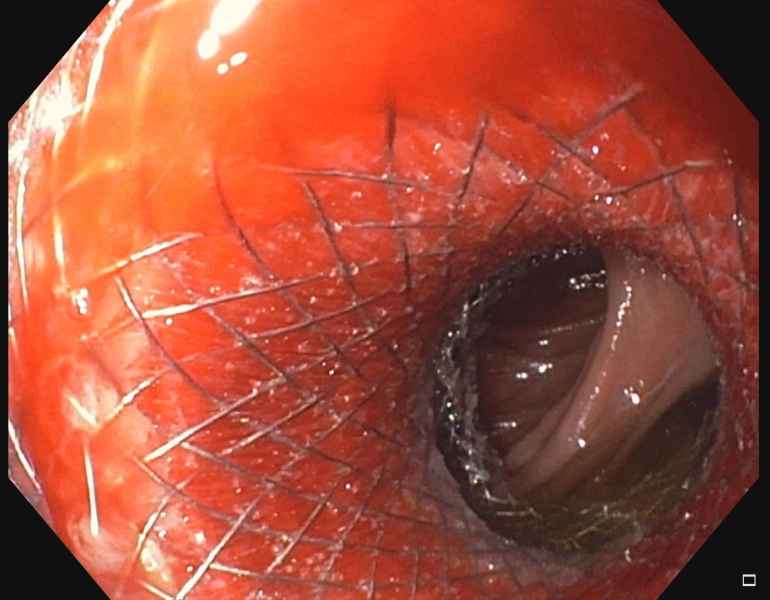

EDGE procedure: esophageal stent to the rescue

Vídeo